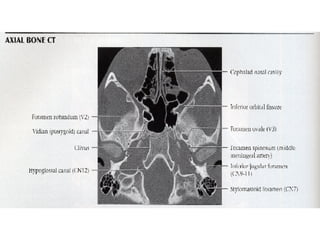

Nervos Cranianos Nervo trigêmeo- V Par 􀂄  Sensitivo 􀂄  Aferente somático geral 􀂄  Gânglio trigeminal - de Gasser 􀂄  N. oftalmico 􀂄  N. maxilar 􀂄  N. mandibular 􀂄  Exteroceptivo e Proprioceptivo

Nervos Cranianos Nervo trigêmeo- V Par 􀂄  Motor 􀂄  Eferente visceral especial 􀂄  M. temporal 􀂄  M. masséter 􀂄  M. pterigoideo lateral 􀂄  M. pterigoideo medial 􀂄  M. milo-hióideo 􀂄  M. digástrico-ventre anterior 1° arco branquial

Nervos Cranianos Nervo glossofaríngeo- IX Par 􀂄  Sensitivo 􀂄  Aferente visceral geral 􀂄  1/3 posterior da língua 􀂄  Faringe 􀂄  Úvula 􀂄  Tonsilas 􀂄  Tuba auditiva 􀂄  Seio e Corpo carotídeo

Nervos Cranianos Nervo glossofaríngeo- IX Par 􀂄  Motor 􀂄  Eferente visceral geral 􀂄  Parótida-Parassimpático

Nervos Cranianos Nervo hipoglosso- XII Par 􀂄  Motor 􀂄  Eferente somático 􀂄  M. língua